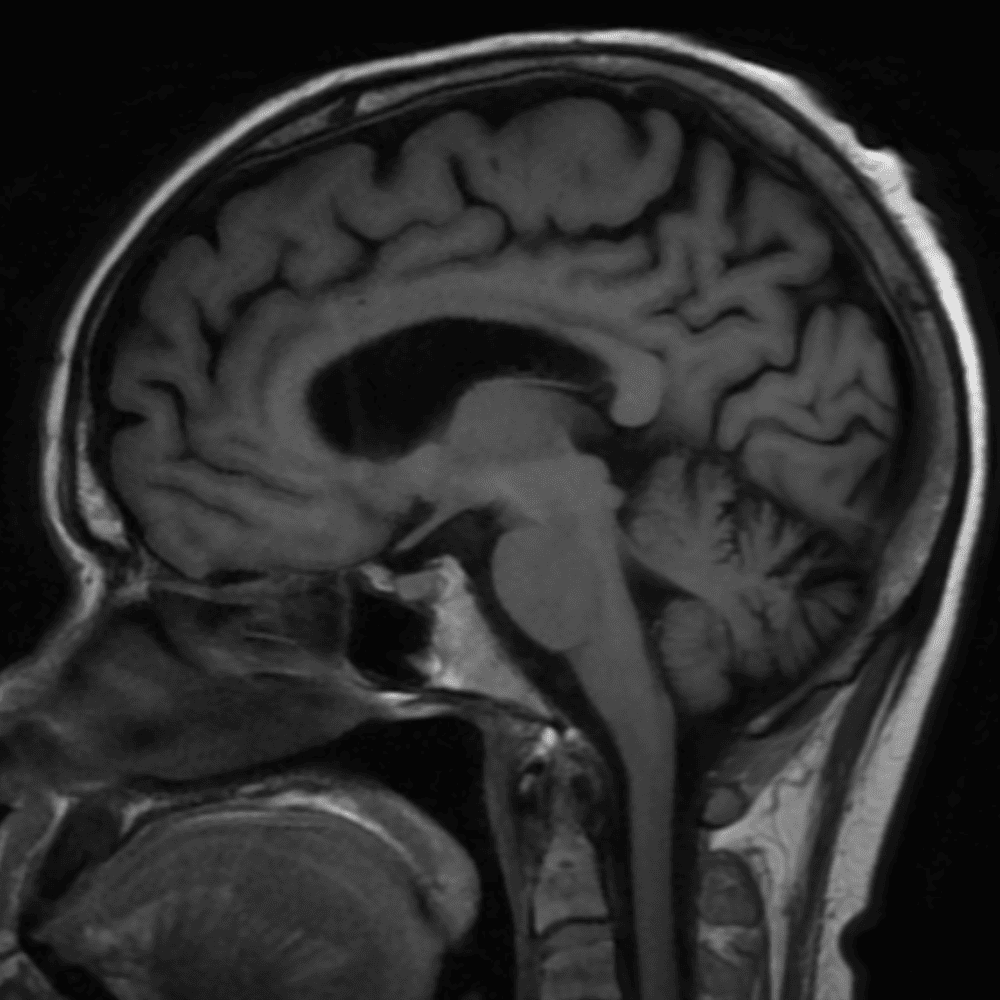

๋‹น์ง ์‹œ ํ”ํžˆ ๋ณผ ์ˆ˜ ์žˆ๋Š” ์‚ฌ๋ก€์˜ ์ „ํ˜•์ ์ธ ์˜ˆ๋ฅผ ํฌํ•จํ•ฉ๋‹ˆ๋‹ค.

๋ฏธ๋ฌ˜ํ•˜๊ฑฐ๋‚˜ ์–ด๋ ค์šด ์‚ฌ๋ก€์™€ ์ผ๋ถ€ ์ •์ƒ ์‚ฌ๋ก€๋ฅผ ํฌํ•จํ•˜์—ฌ ๋‹น์ง์„ ์‹œ๋ฎฌ๋ ˆ์ด์…˜ํ•ฉ๋‹ˆ๋‹ค.